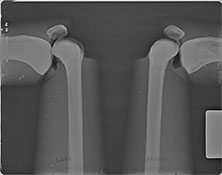

BREAK-APART PIXY Pelvis X-Ray BREAK-APART PIXY Knees X-Ray 1 BREAK-APART PIXY Knees X-Ray 2